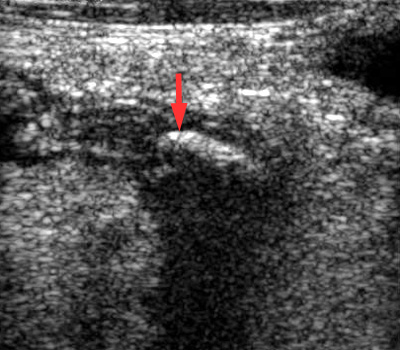

| US confirms a dilated appendix with the calcified appendicolith. | CT confirms the calcified appendicolith and findings of appendicitis. |